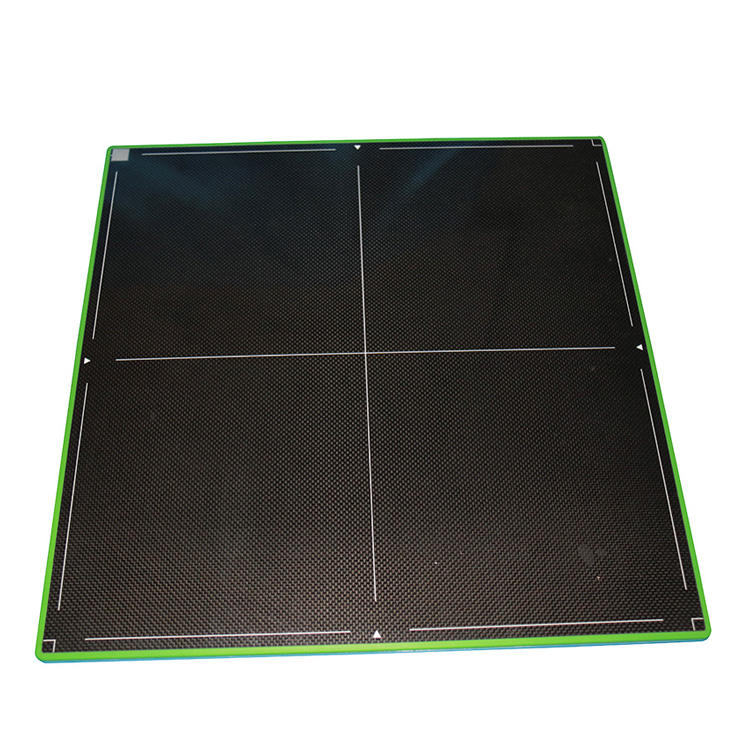

The MSLCV08 is a 17X17 box-type wireless portable flat panel detector designed for human digital radiography.

4. Cassette Flat Panel Detector